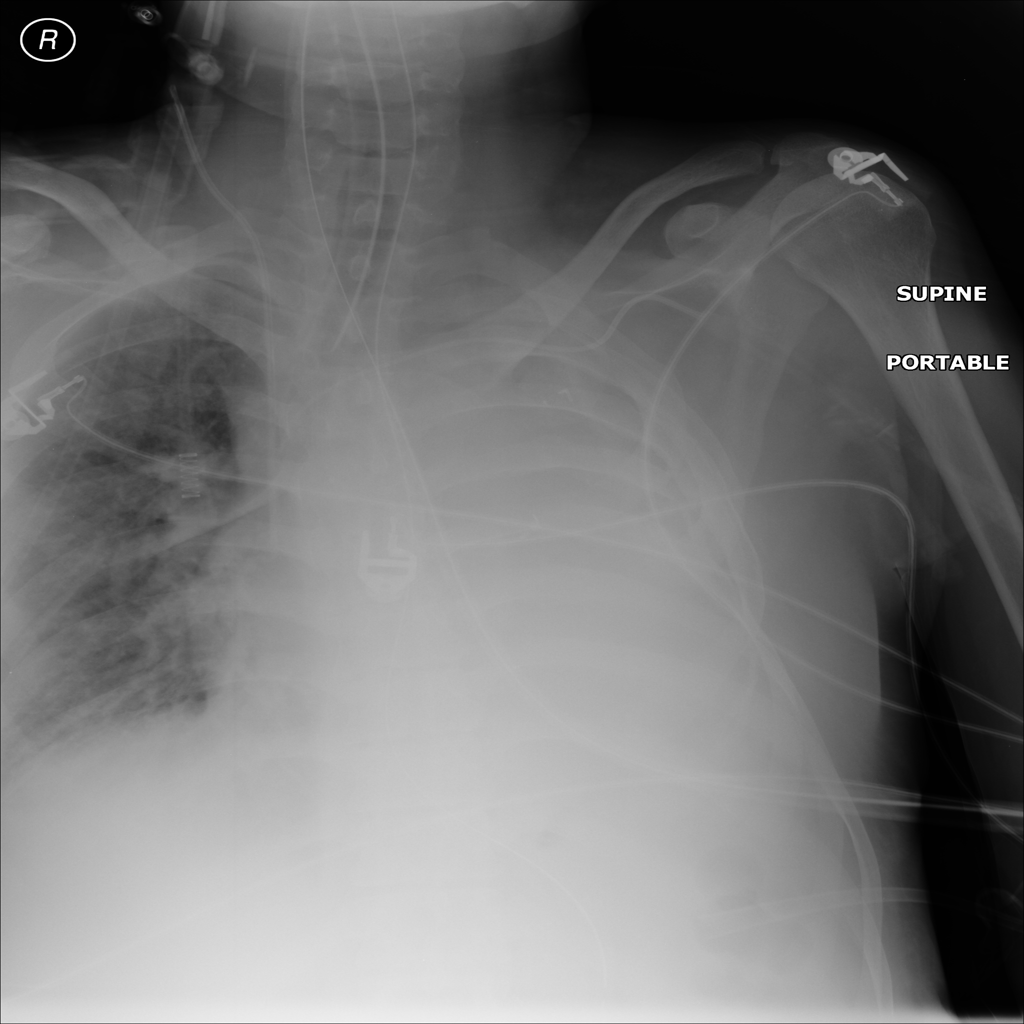

PAT-DB80 · IMG-000Atelectasis

PAT-DB80 · IMG-000

PA